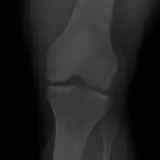

Over 2,100 interactive radiology cases, curated by radiologists for your level of training. Scroll, window, and view cases full screen — just like on PACS. Click linked findings in each writeup to jump straight to them on the image. Cases include sample reports, a focused discussion section, original illustrations, and videos.

完全交互式病例,配备您在 PACS 上期待的各项工具——滚动、调窗、缩放、平移、测量、ROI 和全屏模式。

丰富的标注直接在病例图像上突出关键发现。点击病例讲解中的关联发现,即可跳转至其在扫描上的精确位置。